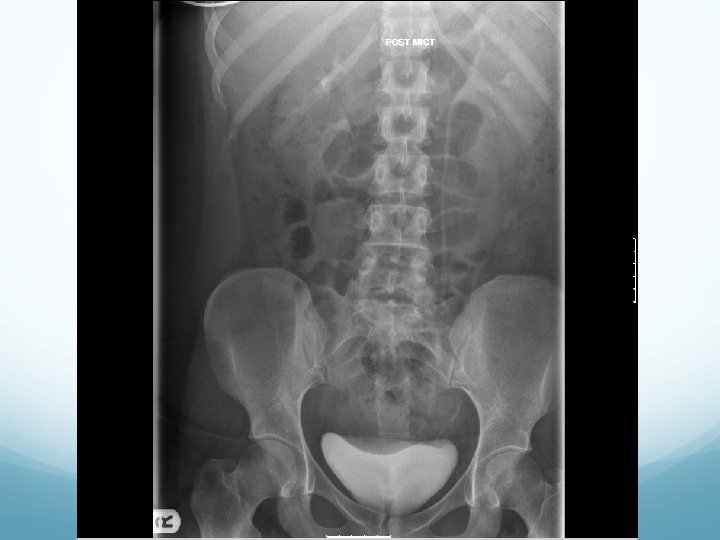

What to look for on an IVU � ALWAYS look at KUB first � CT KUB is gold standard, and only option if U+Es are abnormal 1. Nephrogram � � Contrast in kidney Persistent increasingly dense nephrogram in obstruction 2. Pyelogram � Calyces: � � � ? clubbed / more prominent Extravasation of contrast Ureters: � � � Peristalsis: Normal Dilatation Standing column